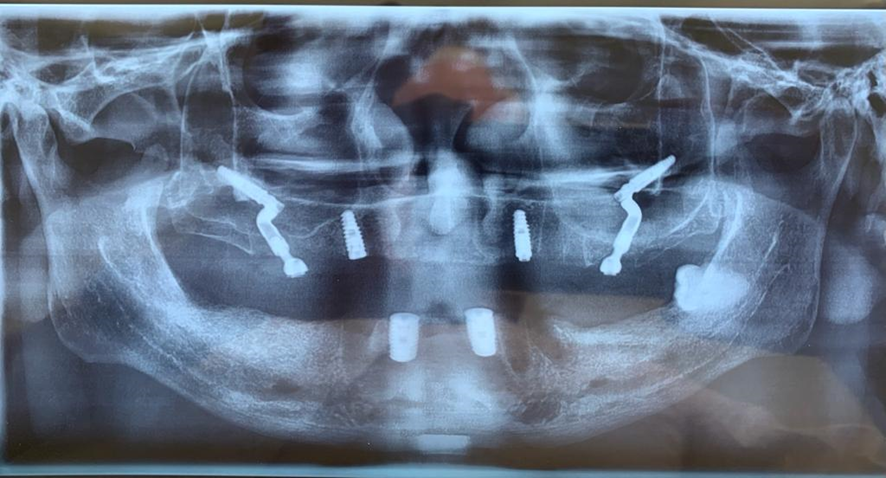

2- Imagens e modelos: TC maxila estendida, se possível compatíveis com programas digitais (Dental Slice, ImplantViewer, ICat Vision e outros);

Caso 1 – Híbrido: dois Pilares Z e dois implantes convencionais

Caso 2 – Protocolo com quatro fixações

O posicionamento, junto ao rebordo alveolar, das plataformas dos Pilares Z, deverá ser aproximadamente próximo ao 16/26 para distais e próximo ao 12/21 para mesiais, configurando assim o polígono de Roy.